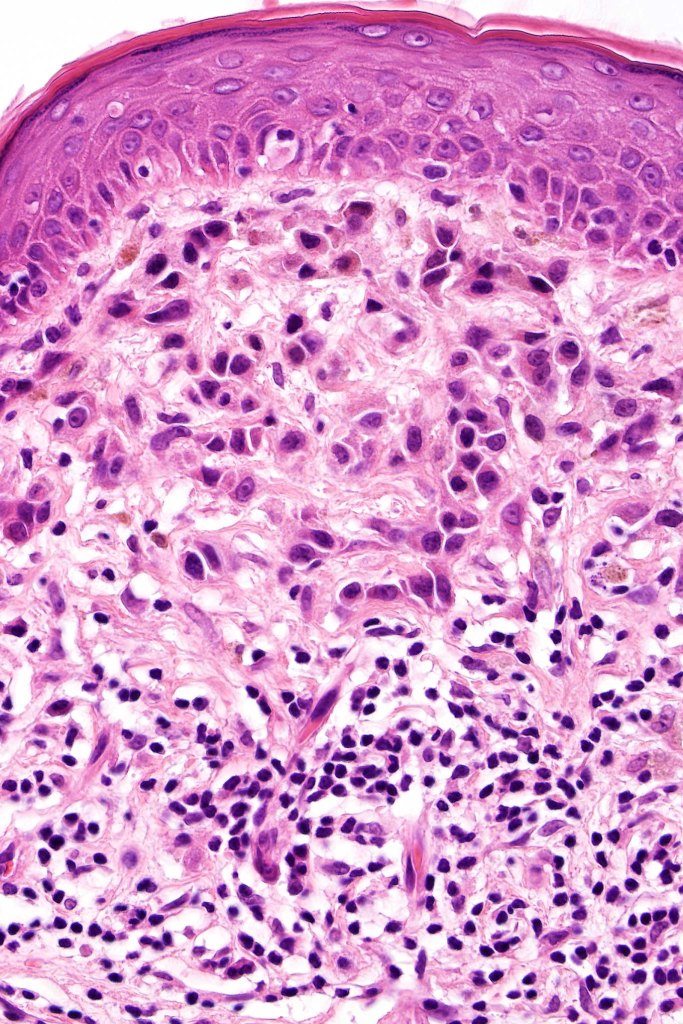

This is uncommon and presents clinically with a history of recent change in color of a common or less often congenital nevus causing concern for melanoma by the clinician. Some, but not all are probably deep penetrating and combined nevus variants. Others may represent follicular type-A cell nests. It is characterized by the presence of deep nest(s) of type -A nevus cells surrounded by & with overlying type-B nevus cells.